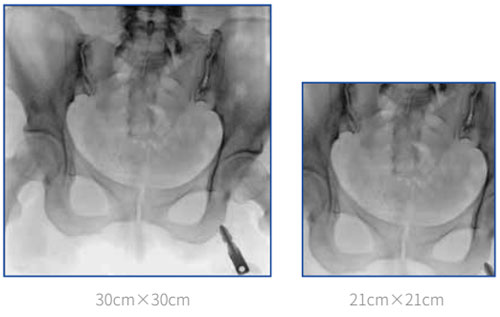

Entire pelvic imaging

lmage taken by 30cm x 30cm FPD can basicly cover the entire pelvic floor. In the surgery of bilateral-pevic fractures or pelvic ring internal fixation, all the fracture sites can be revealed by single exposure, which significantly improves overall efficiency.